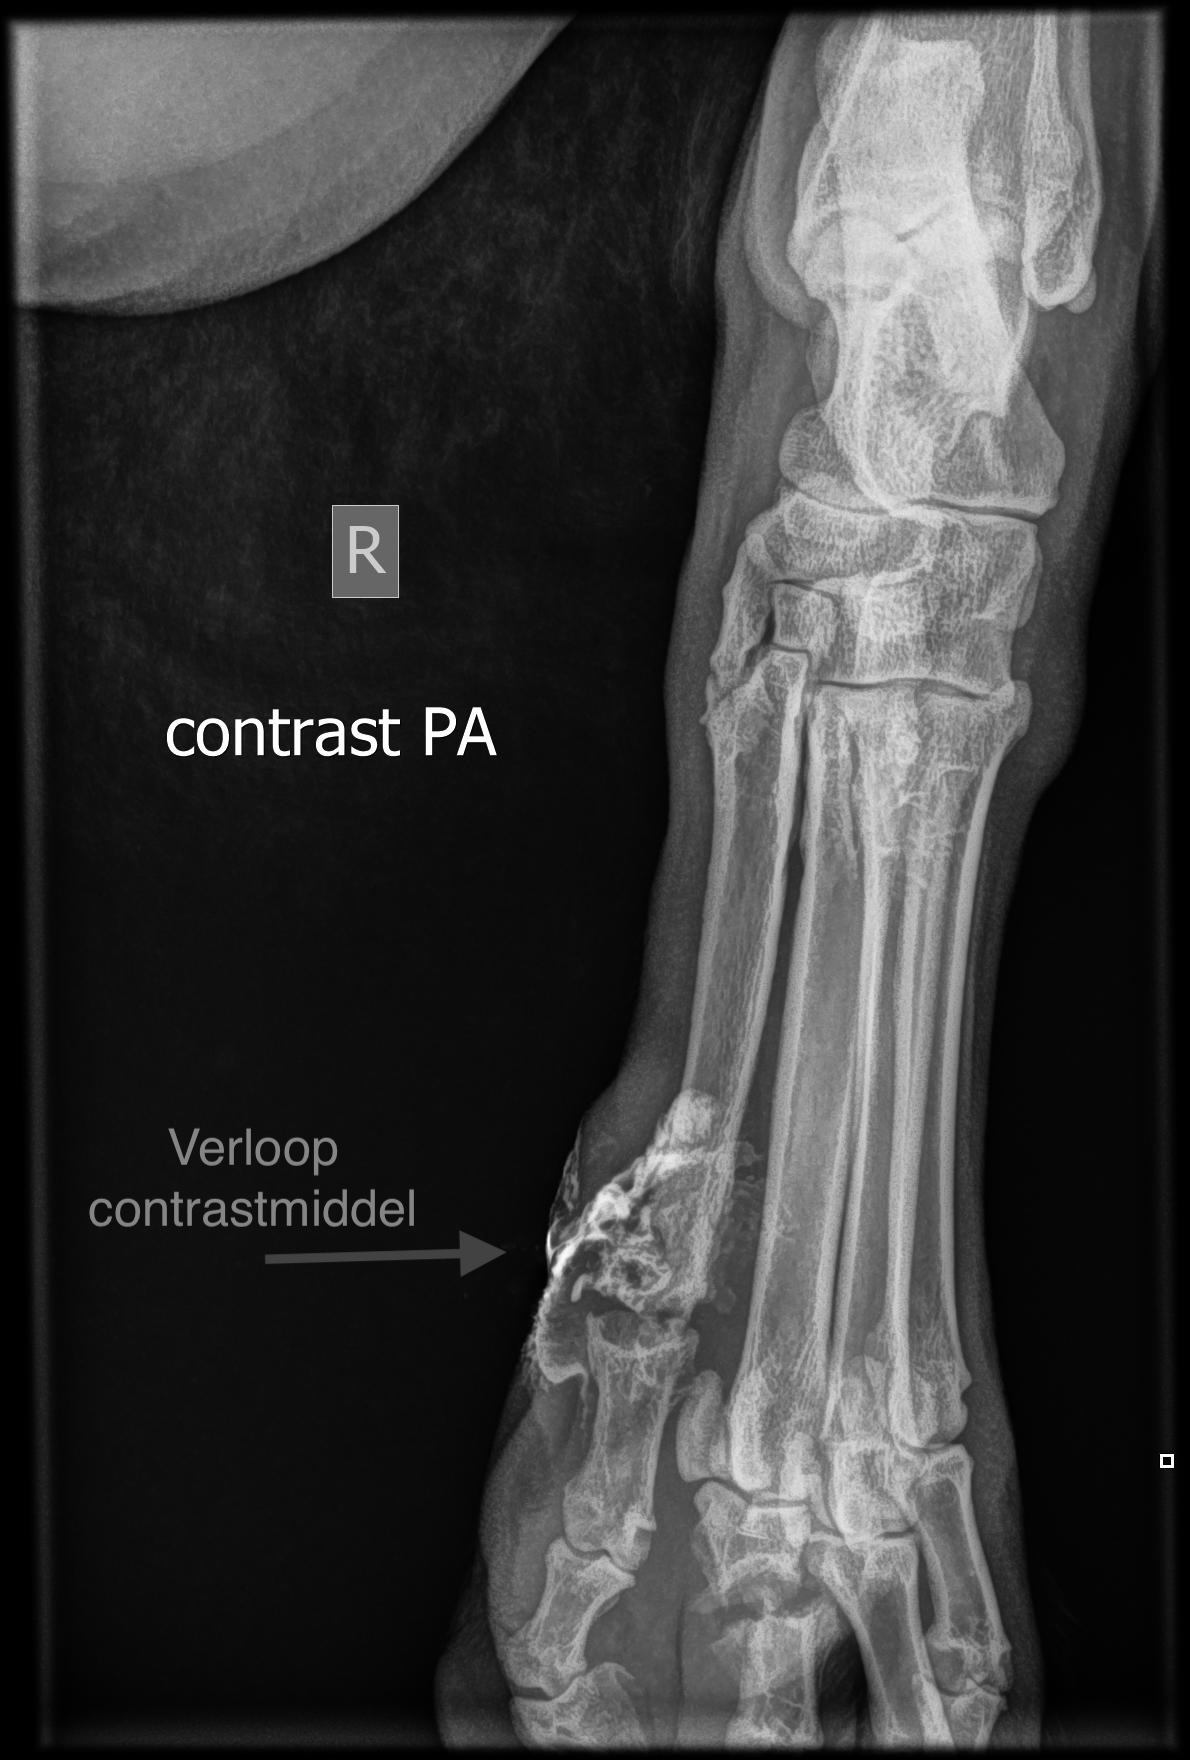

Maar tot onze schrik zagen we op de röntgenfoto ook dat een teenkootje van de andere teen gebroken was. Als hij een teen mist, zal deze gebroken teen harder moeten werken. We hadden nu twee problemen: een fistelende teen met bacteriën (te zien aan het contrastmiddelverloop) en een gebroken teenkootje. We gingen aan de slag: de teen werd verwijderd en een spalk voor de ondervoet werd aangemeten. Het gebroken kootje kon daardoor rust krijgen en gaan helen, terwijl we de operatiewond konden verbinden.